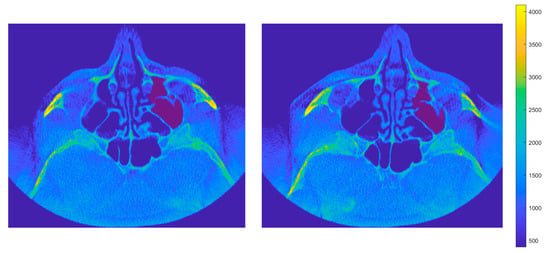

2.2. Algorithm for Detection of the Maxillary Sinus

- Maxillary sinus identification in each image: For a given image, surfaces associated with the sinus volume are determined by checking whether pixels in the upper and lower planes are contiguous with pixels of equivalence classes in the current plane. Let be the set of equivalence classes in plane k; then

- Iterative volume refinement: After each iteration, newly detected pixels are checked for contact with previously undetected equivalence classes in adjacent slices. If such contact exists, the algorithm traverses the images in reverse to incorporate them. This process continues until no new pixels are added. Finally, the images are scanned in normal order to associate any remaining pixels with the sinus volume.